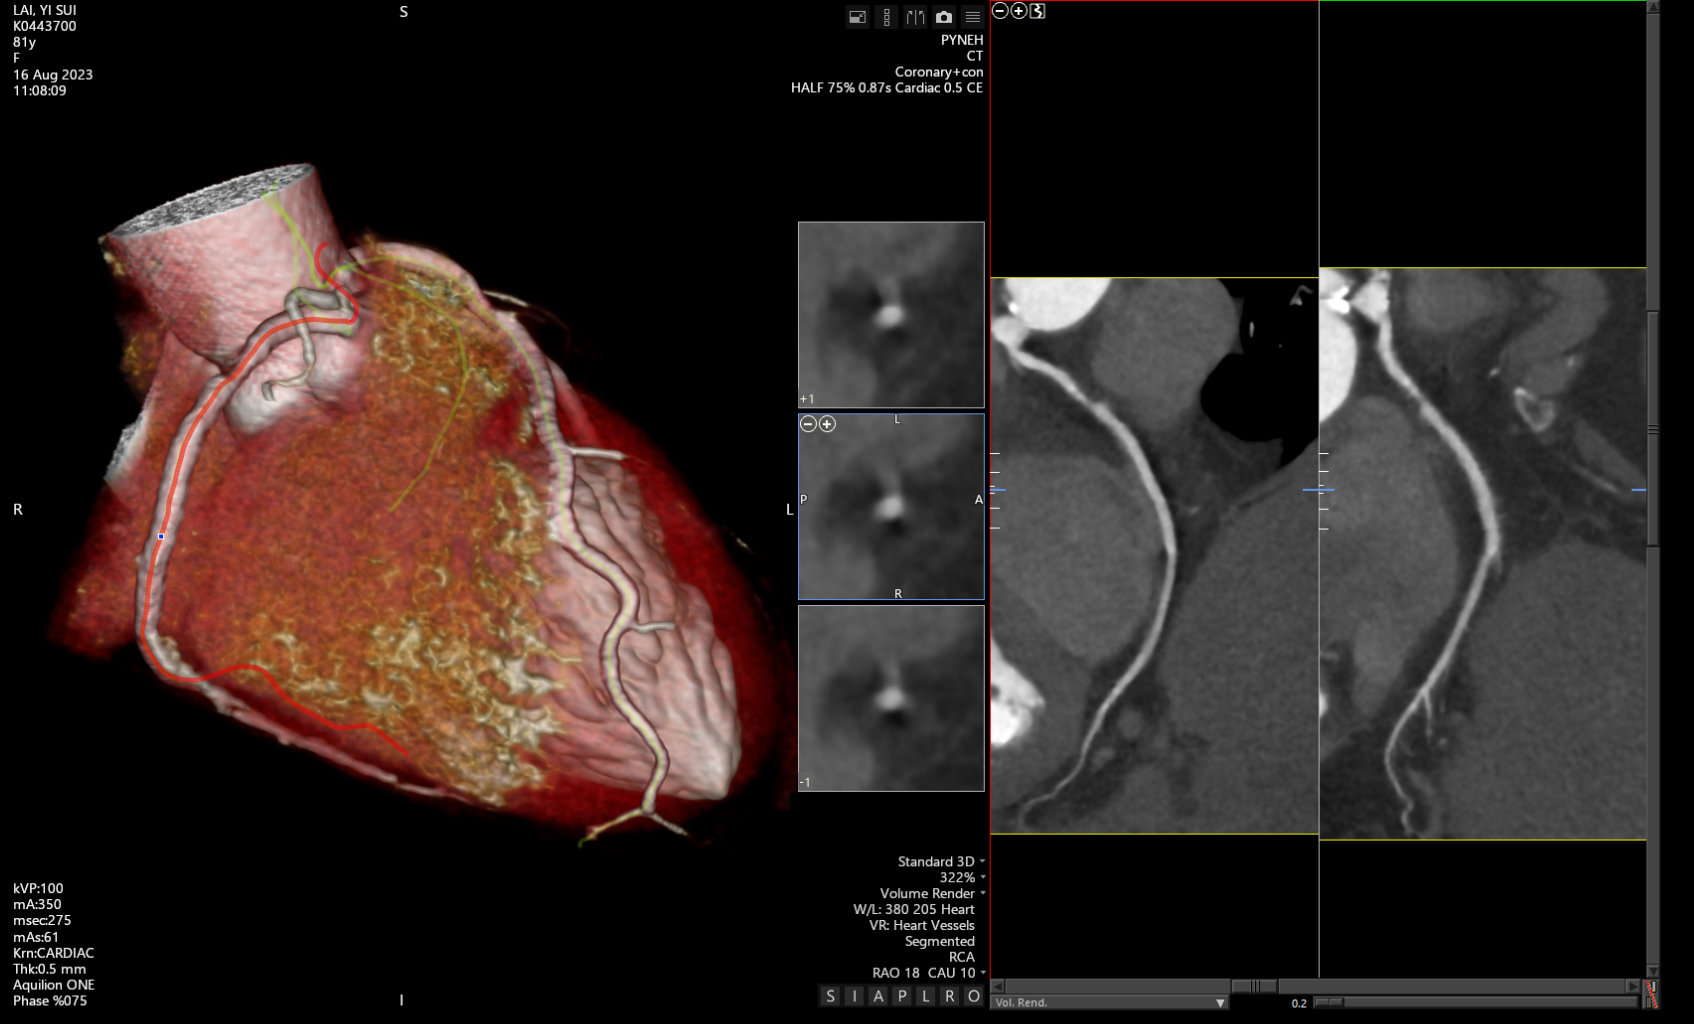

An 83 year-old female with diabetes, dyslipidaemia, and chronic renal disease presented with worsening angina since January 2025. She had CT coronary angiogram done in February 2023, which showed moderate RCA disease. Her symptoms were well-controlled until early this year and was referred for revascularisation. PCI was performed but complicated with distal wire trauma with perforation. The perforation site was successfully managed by Vicryl embolisation.

Baseline renal function showed an eGFR 50 mL/min/1.73m2. Hemoglobin A1c 6.8% and LDL-c 2.6 mmol/L.ECG showed normal sinus rhythm.CT coronary angiogram in 2023 showed moderate proximal RCA stenosis.

Coronary angiogram on 14 January 2025 showed mid LAD 20% and proximal RCA 80% stenosis.